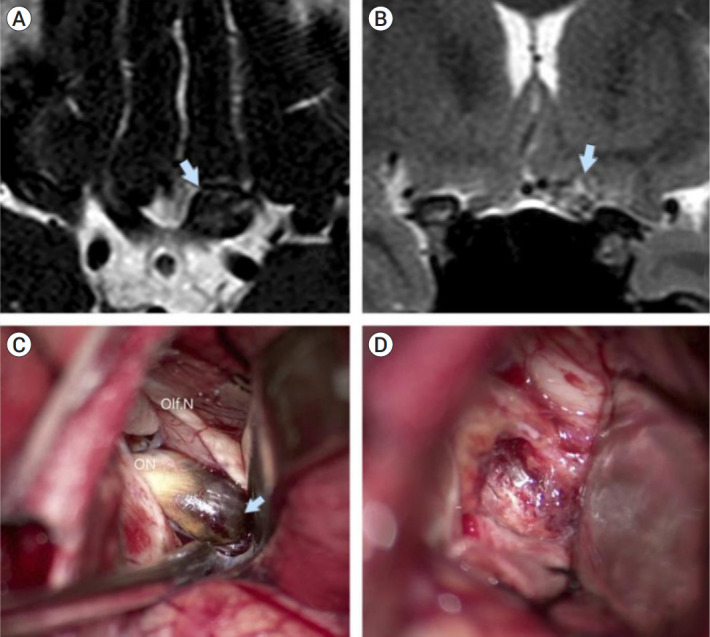

Objective: Optochiasmatic cavernoma is an extremely rare cerebral lesion. They account for approximately 1% of all cavernomas of the central nervous system. Reports on this pathology are limited. Abrupt visual deterioration is a common symptom of the disease. Treatment strategy and visual outcomes after different treatment approaches remain a subject for discussion.

Methods: Patients operated in a period 2005-2021 were analyzed in this study. All patients preoperatively underwent computed tomography (CT) scan, CT-angiography, and magnetic resonance imaging (MRI). Visual function of the patients was assessed pre-op, post-op and at the follow-up. Duration of visual dysfunction was noted as well. Surgical details were also extracted from medical notes. All patients were followed up, and control MRI was performed one month after operation. We assessed surgical series of optochiasmatic cavernomas published for last 10 years. Further comparative analysis with our data was performed.

Results: Five patients were included into this study. There were four men and one woman. Mean age comprised 33.8 years (range 20-48 years). Most patients were admitted to our hospital due to visual disturbances (80%). Visual function improved in four patients. Visual function was unchanged in one patient, lacking visual disturbancies pre-op. Complication developed in one patient.

Conclusions: Optochiasmatic cavernomas are encountered extremely rare. Despite the use of contemporary diagnostic options, differential diagnosis remains challenging. Full diagnostic work-up is mandatory. After the diagnosis is made, surgical treatment should be considered first. Total microsurgical or endoscopic transsphenoidal removal of the optochiasmatic cavernoma is a relatively safe and effective treatment method facilitating improvement of visual function.